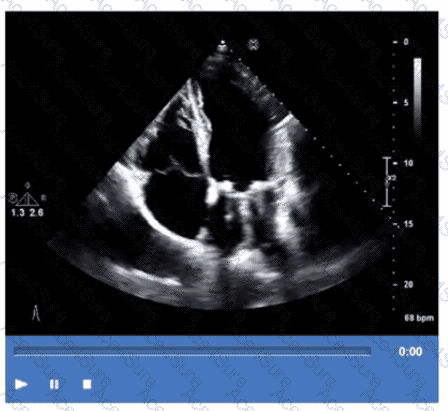

The echocardiographic video shows a prosthetic ring-like structure attached to the mitral annulus with preserved native leaflet motion, consistent with an annuloplasty ring repair. Annuloplasty rings are used to reduce the mitral annulus size and improve leaflet coaptation in mitral regurgitation without replacing the valve.

Bioprosthetic or mechanical valve replacements would show distinctly different echogenic valve structures with leaflet or disc motion replacing the native valve. Extensive calcification of a native valve appears as echogenic, thickened leaflets without a discrete ring.